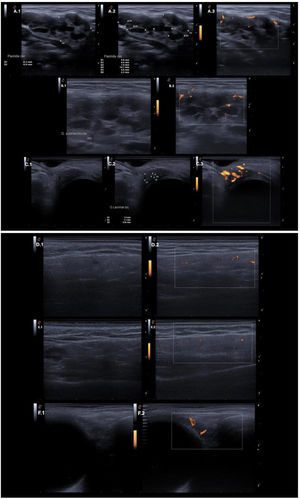

With a clinical suspicion of IgG4-RD, an ultrasound evaluation was performed using an ESAOTE ultrasound system with a high-frequency IHX 6-25 linear transducer (3–22MHz), gain settings of 50–80%, and a depth of 1–2cm. Power Doppler analysis of the salivary glands was conducted following the scoring system proposed by Zhou et al. (Table 1), yielding a total score of 32 points. Ultrasound assessment of the lacrimal glands revealed parenchymal heterogeneity, the presence of hypoechoic areas, and positive power Doppler findings, further supporting the diagnostic suspicion (Fig. 2). These findings suggested the diagnosis of IgG4-RD but warranted confirmatory studies and further evaluation to rule out differential diagnoses (Table 2), these evaluations ruled out infectious and oncologic diseases, as well as Sjögren's syndrome and sarcoidosis.

Ultrasound findings of salivary and lacrimal glands. Ultrasound findings of the salivary and lacrimal glands in the initial assessment and after pharmacological management. Panel (A) Right parotid gland. Evident heterogeneity in A.1. Anechoic patchy areas between 6mm and <15mm in A.2. Positive Doppler signal in A.3. Panel (B) Left submandibular gland. Evident heterogeneity and anechoic patchy areas between 6mm and <15mm in B.1. Positive Doppler signal in B.2. Panel (C) Left lacrimal gland. Evident heterogeneity in C.1. Anechoic patchy areas <6mm in C.2. Abundant Doppler signal in C.3. Panel (D) Right parotid gland after treatment. Parenchymal echogenicity similar to the thyroid in D.1. Mildly positive Doppler signal in D.2. Panel (E) Left submandibular gland after treatment. Parenchymal echogenicity similar to the thyroid, minimal heterogeneity with a hypoechoic area between 6 and 15mm in E.1. Mildly positive Doppler signal in E.2. Panel (F) Left lacrimal gland after treatment. Parenchymal echogenicity similar to the thyroid in F.1. Mildly positive Doppler signal in F.2.

The patient tolerated steroid dose reduction. Within the first 15 days, a decrease in the size of the lacrimal and parotid glands was observed, along with improved parenchymal echogenicity, resembling that of the thyroid gland. There was a reduced proportion of hypoechoic areas compared to the initial evaluation, with patchy regions measuring less than 6mm (previously 6–15mm). Additionally, a decrease in power Doppler signal intensity was noted (see Table 1 and Fig. 2). The follow-up Zhou score was recorded at 11, remaining within the classificatory range but showing a significant reduction compared to the initial assessment. The lacrimal glands demonstrated a marked decrease in size, along with a substantial reduction in power Doppler findings. At 30 days after the last Rituximab infusion, a pronounced reduction in the size of the lacrimal and salivary glands was documented (Fig. 2), as well as improvement in the ureteral lesion. The patient continued treatment with prednisolone 5mg, methotrexate, and completed the Rituximab infusion regimen.

In this patient, parotid heterogeneity was observed with patchy anechoic areas measuring between 6mm and <15mm, along with a strongly positive power Doppler signal. Similar findings were noted in the submandibular and lacrimal glands. These abnormalities could serve as early indicators of disease, enhance diagnostic accuracy, and influence disease progression through early treatment initiation. Although lacrimal glands are not currently included in this scoring system, we documented similar alterations in this case, suggesting that future refinements to the scoring criteria may improve the diagnostic performance of ultrasonography in IgG4-RD. However, the external validity of such diagnostic strategies remains to be established.